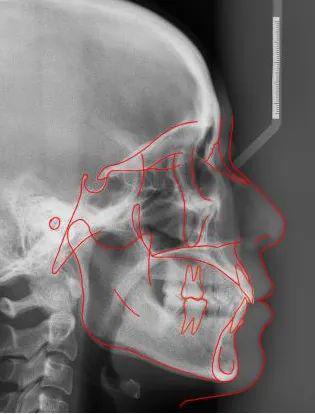

牙齿矫正头颅侧位片是正畸诊断中不可或缺的影像学检查,通过拍摄头颅侧位方向的X光片,全面评估颅颌面骨骼、牙齿及软组织的形态与位置关系,为制定个性化矫正方案提供精准依据,与普通牙片仅显示牙齿不同,头颅侧位片能捕捉从颅底到颏部的整体结构,揭示牙齿、颌骨与面部轮廓的深层关联,是正畸医生判断错颌畸形类型、预测矫正效果的核心工具。

- 图像质量控制:理想图像需清晰显示蝶鞍、鼻中隔、腭骨、颈椎等骨性标志,以及牙齿、牙根、唇部轮廓等软组织结构,无运动伪影或曝光过度/不足。